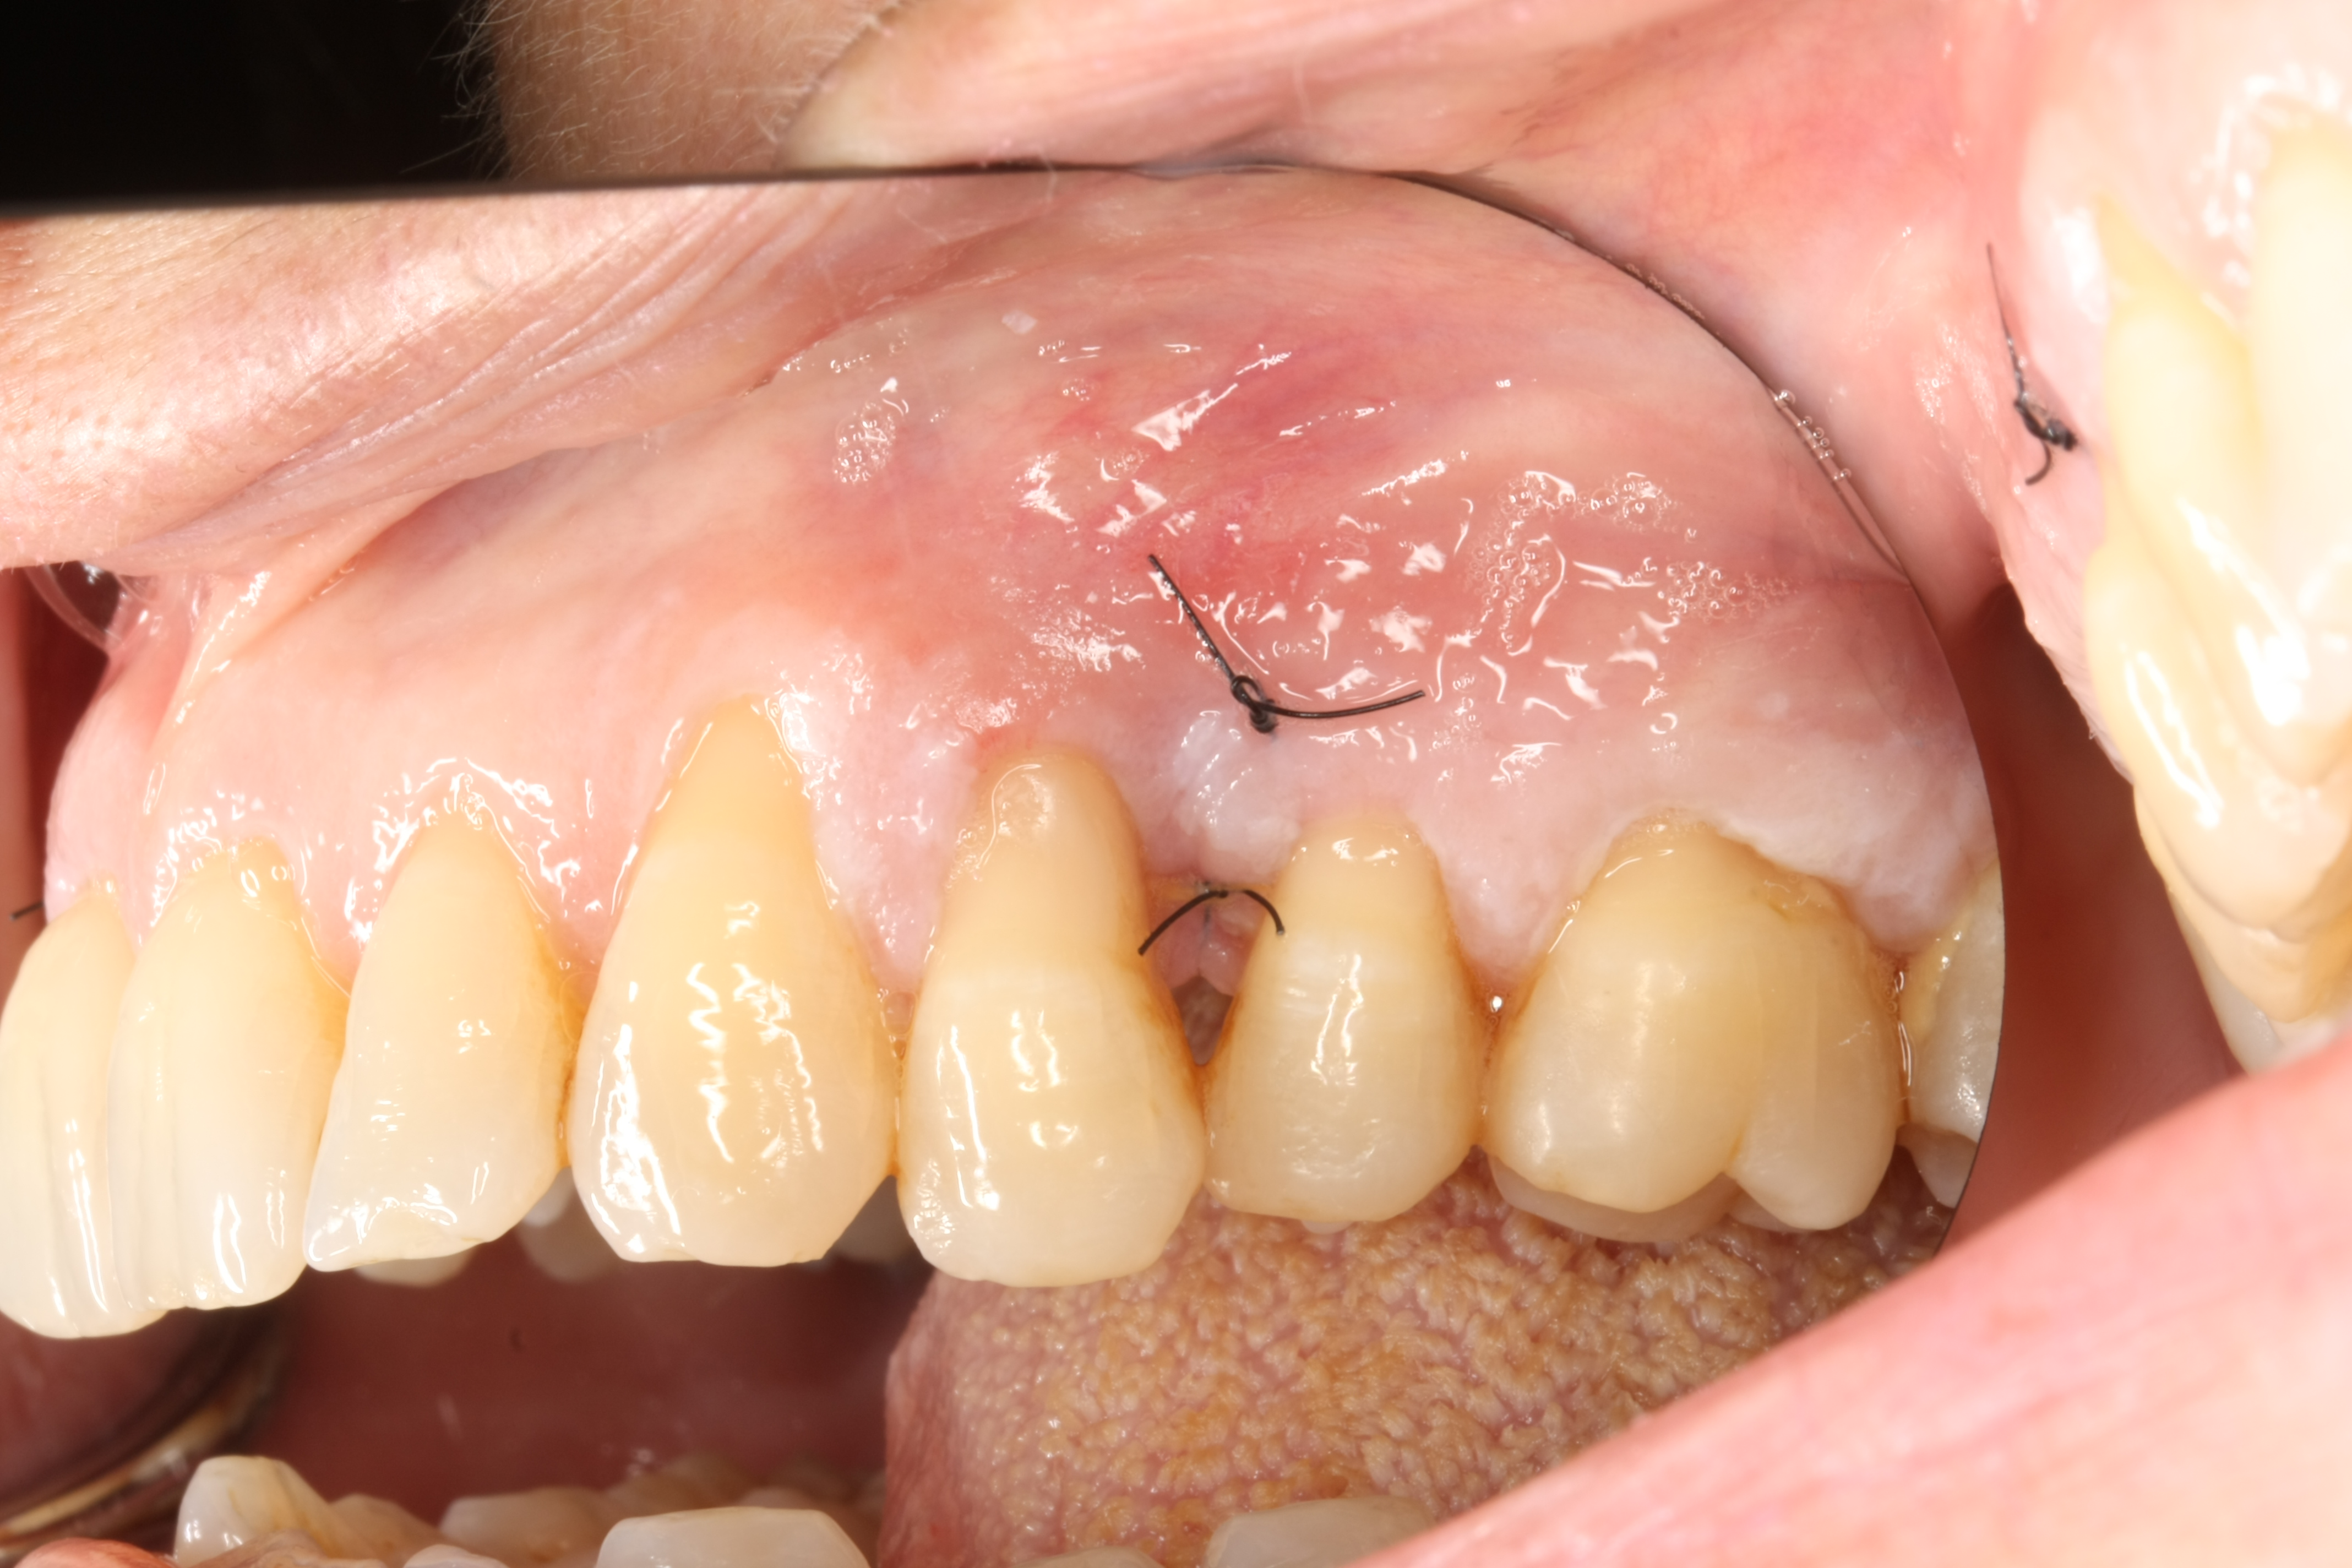

Image C1:2 Post-Operative (Tooth 12)

No bleeding, rapid healing and wound closure with minimal further recession.

Image C1:3 5 Days Post-Operative

Enhanced wound healing and inflammation elimination.